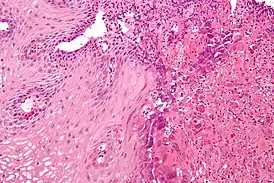

Морфологические формы эзофагита

| Катаральная форма | Характеризуется гиперемией и отёчностью слизистой оболочки пищевода. Наиболее распространённая форма эзофагита. |

| Отёчная форма | Характеризуется гиперемией и отёчностью слизистой оболочки пищевода. Наиболее распространённая форма эзофагита. |

| Эрозивная форма | Чаще всего развивается при острых инфекционных болезнях и действии на стенку пищевода раздражающих веществ. |

| Геморрагическая форма | Развивается при некоторых инфекционных и вирусных болезнях (например, при сыпном эпидемическом тифе, гриппе). |

| Псевдомембранозная форма | Наблюдается при дифтерии, скарлатине. При этой форме фибринозный экссудат не спаян с подлежащими тканями. |

| Эксфолиативная форма | Наблюдается при дифтерии, скарлатине. При этой форме фибринозный экссудат прочно связан с подлежащими тканями. |

| Некротическая форма | Встречается при тяжёлом течении инфекционных болезней, таких, как корь, скарлатина, брюшной тиф и др., а также при кандидозе, агранулоцитозе, сопровождается образованием глубоких язв. |

| Флегмонозная форма | Образуется в результате внедрения в стенку пищевода инфицированного инородного тела, процесс может распространиться вдоль пищевода и в сторону средостения. |